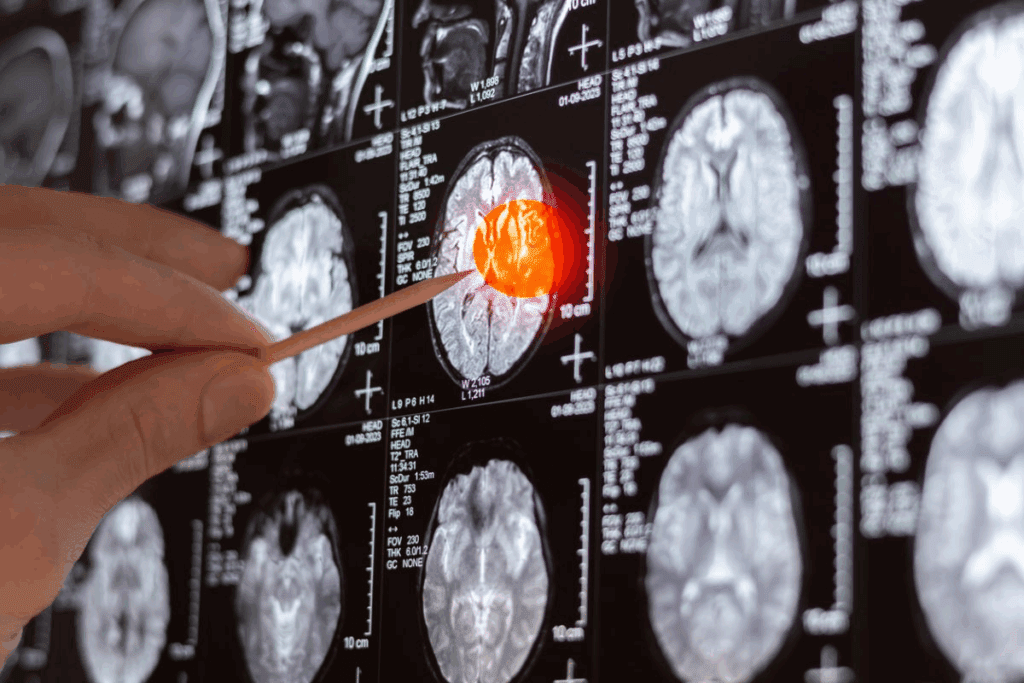

Are Brain Tumors Terminal? The Truth About Survival Rates

Knowing the survival rates for brain tumors is key for patients and their families. A brain tumor diagnosis can change a person’s life. Knowing the survival facts helps in making care decisions.

Survival rates for brain tumors change based on the tumor type, grade, and patient health. The 5-year survival statistics give a general idea of the prognosis for different brain tumors.

5-Year Survival Statistics by Tumor Type

The 5-year survival rate is a key indicator for cancer prognosis, including brain tumors. For example, glioblastoma, a very aggressive brain cancer, has a low 5-year survival rate. On the other hand, meningioma, often benign, has a much higher survival rate.

- Glioblastoma: 22% 5-year survival rate

- Meningioma: 84% 5-year survival rate

- Low-grade glioma: 73% 5-year survival rate

These stats show why knowing the specific brain tumor type and its characteristics is vital for prognosis.